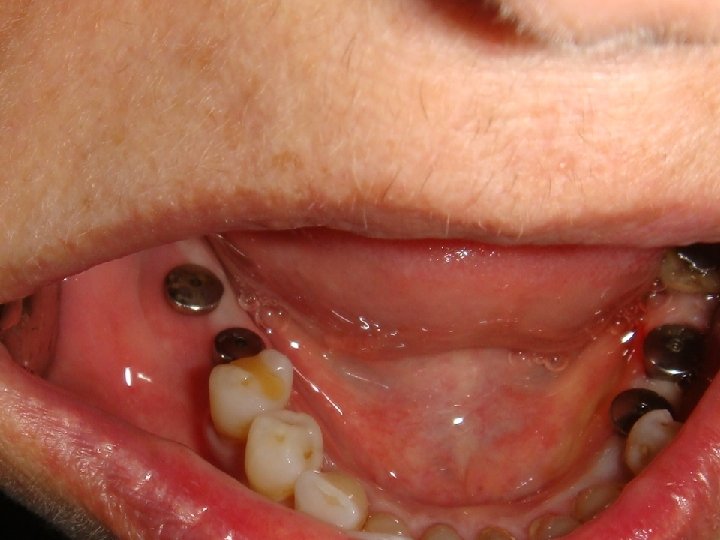

Title No. 2: Innovative Prosthodontics based on a high load capacity of implants

Abstract No. 2: Modern concepts of implant Prosthodontics emphasises an optimal simulation of the lost oral tissues – tooth, bone and soft tissue. The quality of simulation can be defined by several parameters, e. g. the dimension of an occlusal surface, the used dental materials, the type of fastening of the suprastructure, etc.

Abstract No. 2: (cont. . ) Planning implant Prosthodontics is mainly related to the available amount of residual bone and the load capacity of an implant. Especially the bone anchorage and the component strength of an implant limit the construction design of a suprastructure. Therefore to gain a deep insight into biomechanics is a prerequisite for an adequate planning of an appropriate construction design. In case of very high load capacity of an implant the expanded treatment possibilities are: • unsplinted single posterior crowns • physiological occlusal surface • long cantilevers • inclusion of patients with excessive bruxism • short implants • small implant diameter

Abstract No. 2: (cont. . ) The important consequence in the daily work of the last two items - the ability to use short and small implants due to an excellent bone anchorage - is a reduced need of augmentation procedure resulting in a huge increase of patients which accept implant based therapies only with minimal invasive medical intervention. However, an aesthetic result borne on a small implant-diameter requires a creative implementation on the part of the dental technician, taking the surrounding soft tissues (emergence profile) into due account. The submucosal shape of the abutments or the crown should correspond to a natural tooth and should be designed like an ovate-pontic of a bridge.